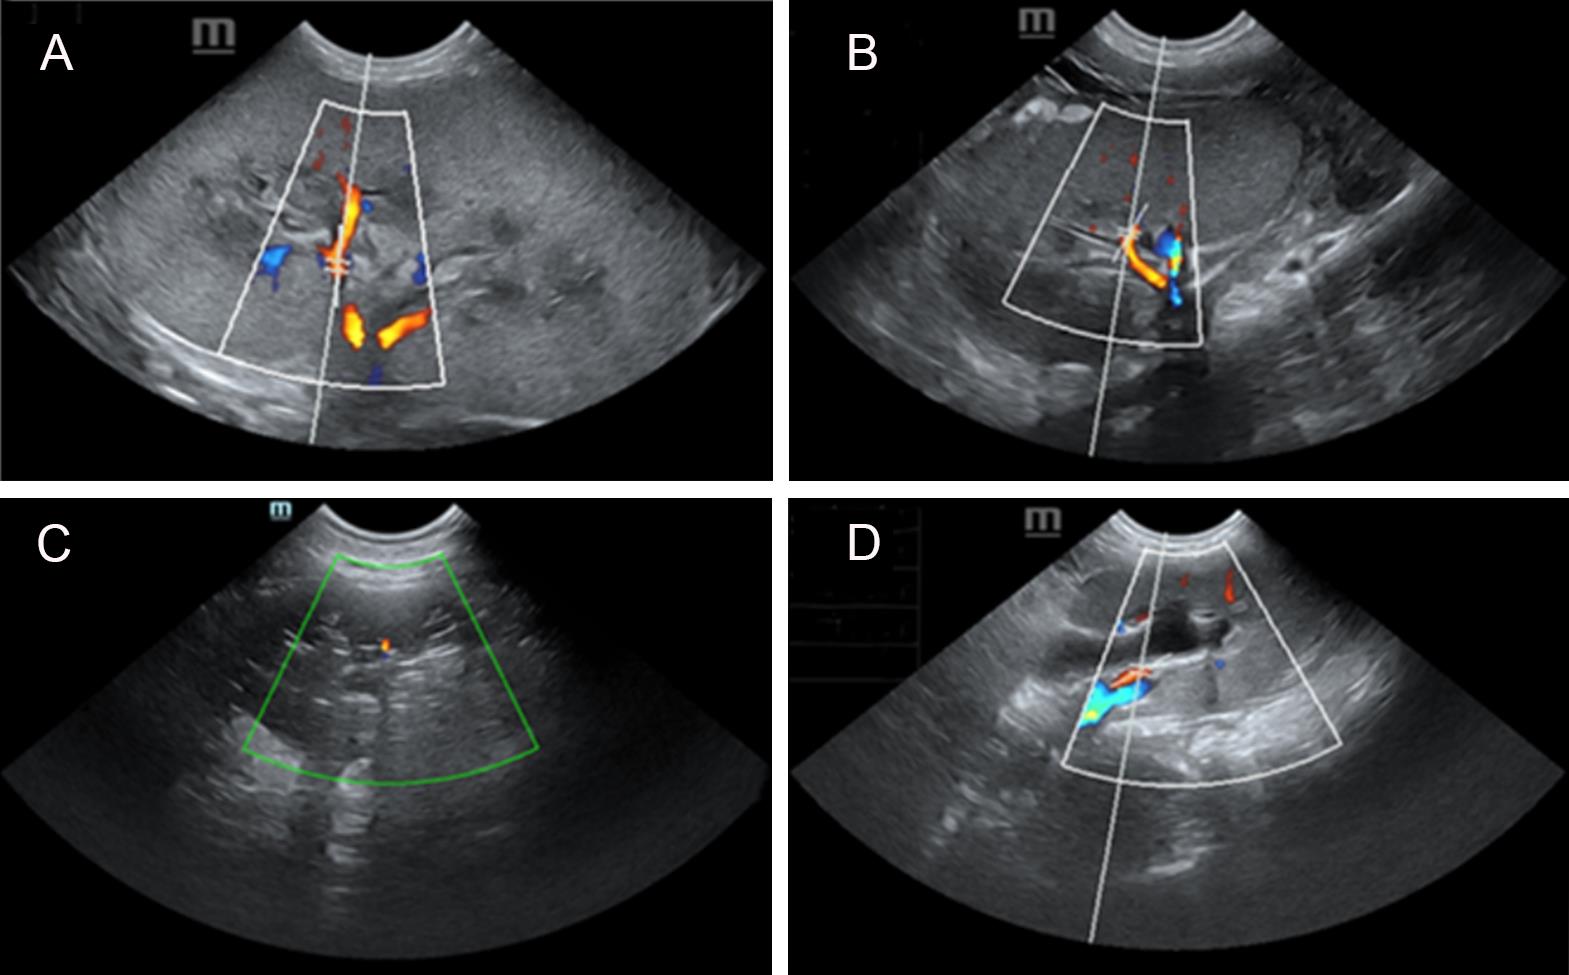

Figure 4 Renal blood flow monitoring of donor and recipient pigsNote: A, Preoperative ultrasound image of pig R; B, Postoperative ultrasound image of pig R at 24 days; C, Postoperative ultrasound image of pig DR1 at 17 days; D, Postoperative ultrasound image of pig DR2 at 17 days.